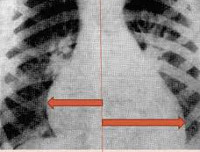

Рентген при выраженном заболевании определяет увеличение размеров сердца.

При рентгенографии органов грудной клетки выявляется кардиомегалия, изменение формы сердечной тени, усиление легочного рисунка за счет венозного застоя, признаки интерстициального отека легких. Результаты УЗИ сердца у ребенка демонстрируют дилатацию полостей сердца, снижение сократительной активности миокарда левого желудочка и фракции выброса.